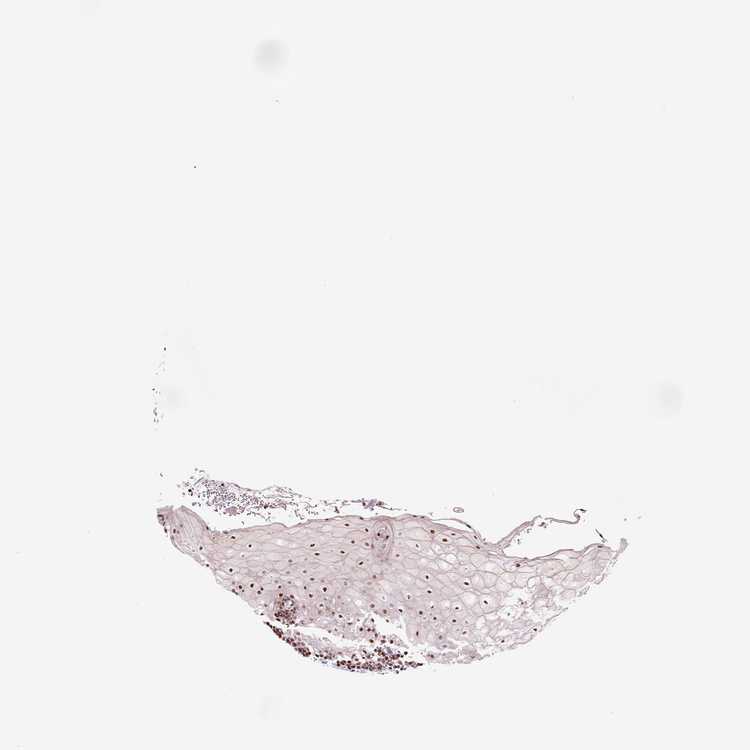

TISSUE PRIMARY DATA ORAL MUCOSA Show tissue menu

ORAL MUCOSA - Antibody stainingi

Antibody staining in the annotated cell types in the current human tissue is reported as not detected, low, medium, or high, based on conventional immunohistochemistry profiling in selected tissues. This score is based on the combination of the staining intensity and fraction of stained cells.

Each image is clickable and will lead to virtual microscopy that enables deeper exploration of all samples and also displays staining intensity scores, fraction scores and subcellular localization as well as patient and tissue information for each sample.

Antibody HPA068771

Squamous epithelial cells Medium